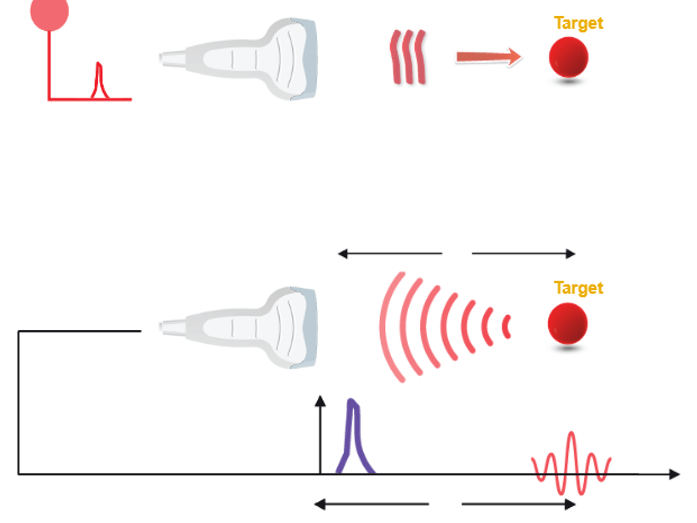

An ultrasound probe emits a pulse in response to electrical excitation. This ultrasonic pulse, transmitted to biological tissues, spreads by degrees.

The echoes are generated by reflection or scattering and propagate backward towards the probe, which operates in receiver mode immediately after the pulse is transmitted. Whenever an echo reaches the surface of the probe, an electrical signal is produced, having an amplitude proportional to that of the echo.

If we consider that an ultrasound wave propagates in the soft tissues at a constant mean speed c, the time t (echo flight time) that elapses between the emission and the reception of an echo, corresponds to the duration of a round trip to the target which is expressed simply by the fundamental relationship of ultrasound: ct = 2z, where c is the ultrasound speed, t is the time of propagation, and z is the penetration distance.

Scanning Technique

However, It is sufficient to perform a large number of different ultrasound shots by shifting the firing axis each time. The position of a point on the screen depends on the flight time of the echo and the position of the corresponding ultrasonic firing axis.

What is Pulse Repetition Frequency? And what does it depend on?

Pulse Repetition Frequency (PRF) is the number of ultrasound pulses emitted by the transducer per second. It depends on the speed of sound and the depth of exploration; Thus it can be altered by changing the depth of imaging. The further the ultrasound travels into the tissue, the higher the PRF becomes.